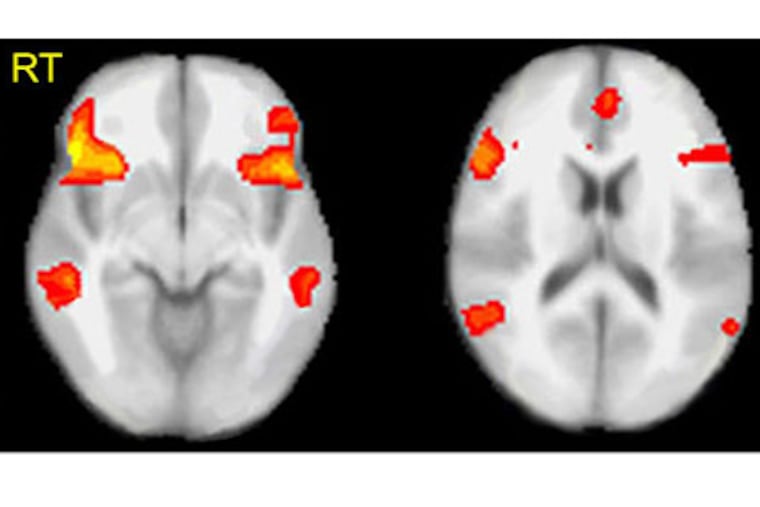

While a polygraph relies on indirect measures, MRI scans reveal the activation of various regions of the brain's cortex that are associated with deception, a visual that would resonate with a lay audience, he said.

Each person underwent the process while hooked up to a polygraph device and while undergoing a functional MRI scan, a type of scan that can be performed in high-end MRI machines. The results of each were evaluated by three raters.

Two out of three polygraph experts correctly detected the lies on 20 out of 28 occasions, whereas two out of three MRI raters correctly detected 24 out of 28 lies. Overall, the MRI raters were 24 percent more likely to detect the lie in any given participant, a difference the authors found to be statistically significant.